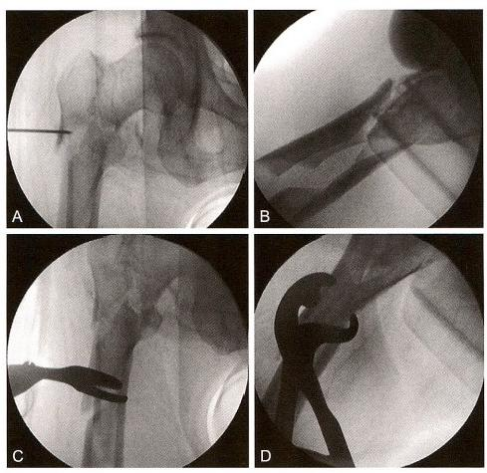

(1)**步:复位导针定位。

撬拔技术:先用4mm 克氏针经皮插入,纠正近端前屈、外展、外旋, 然后开口定位(图12-3)。

(2)第二步:开口。

复位手指技术:开口后用“复位手指”器进行复位(图12-4)。

图12-3 复位与开口

图12-4 开口后“复位手指”器复位